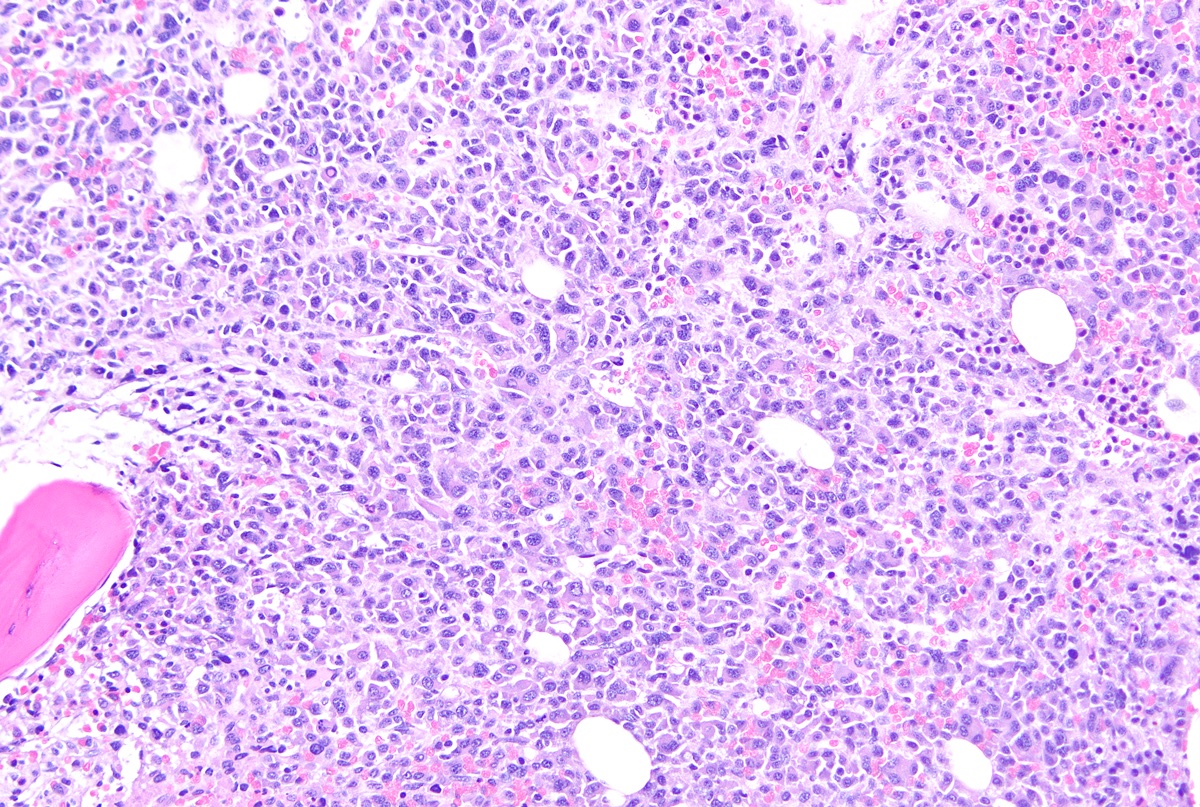

Microscopic (histologic) description

- Core biopsy (Am J Clin Path 1987;87:342):

- Interstitial clusters, nodules or sheets of plasma cells

- Areas of bone marrow may be spared with preserved hematopoiesis, other cases may have diffuse involvement and markedly suppressed hematopoiesis

- Prominent osteoclastic activity may be seen

- IHC to quantify plasma cells (CD138), stains for Ig kappa and lambda to establish clonality

Microscopic (histologic) images

Contributed by Genevieve M. Crane, M.D., Ph.D. and Tapan Bhavsar, M.D., Ph.D.